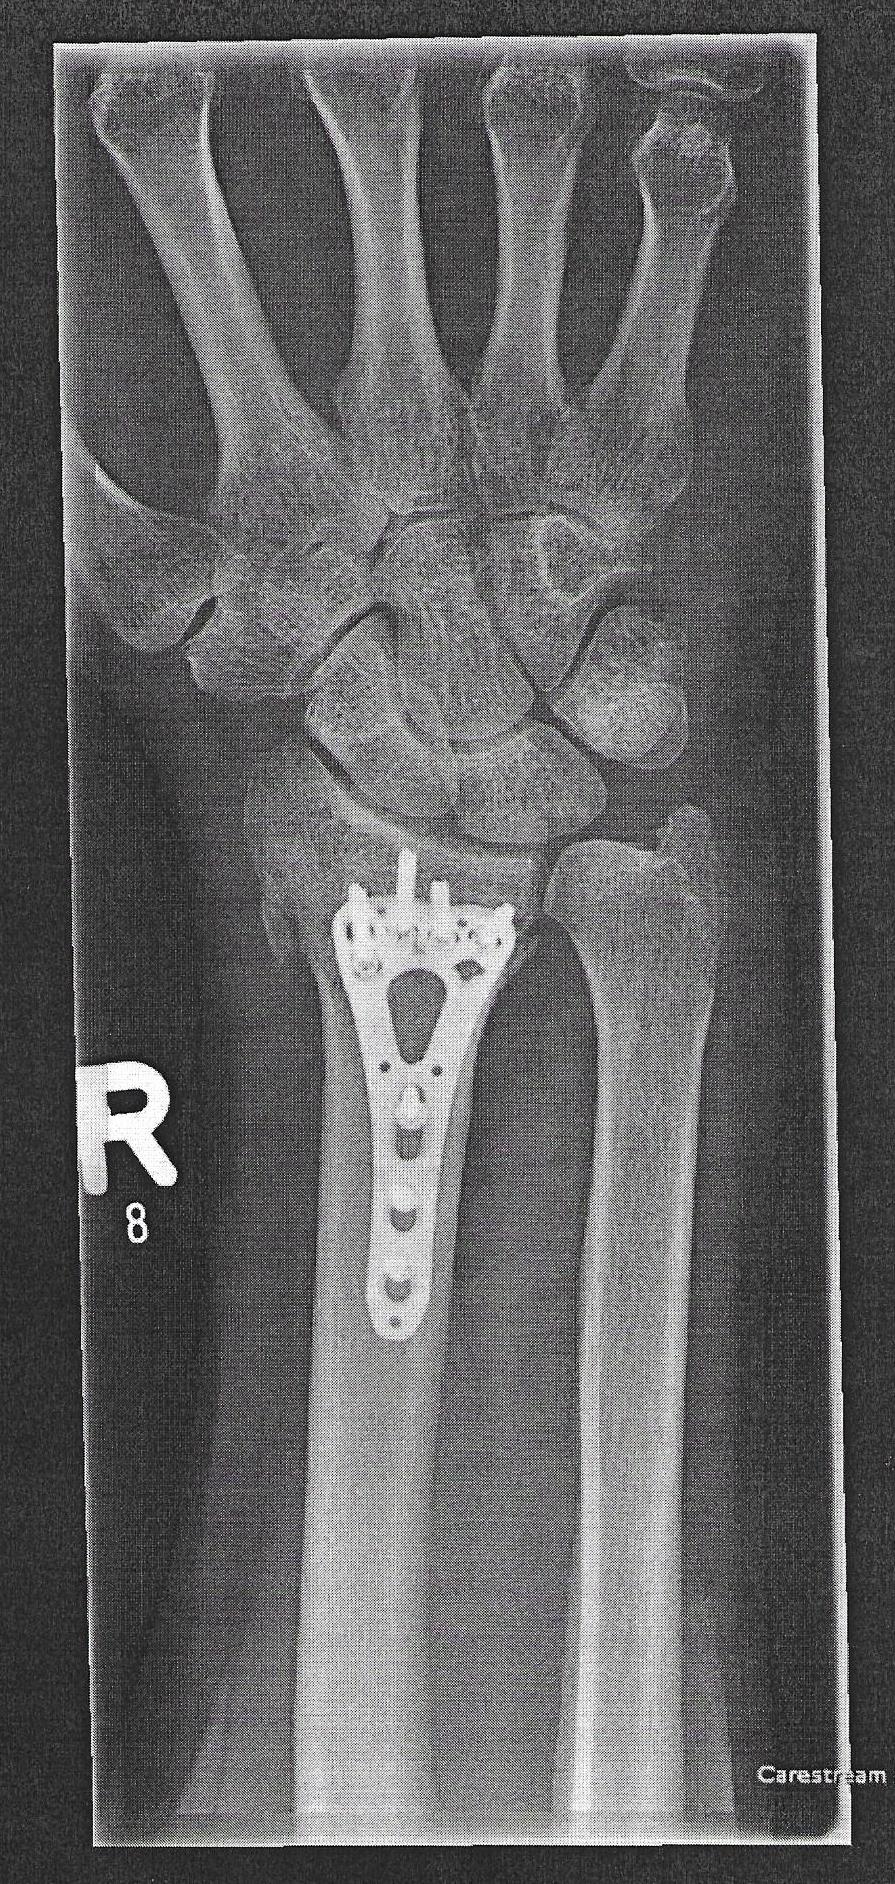

Nein, ist wirklich vergessen, dass vielleicht zu viel Gewebe zugewachsen ist, war auch 2 Jahre nach der Installation. Außerdem machen sie nicht "automatisch" ein Foto nach der OP.vergessene Schraube? die sieht man doch auf jedem billigen Rötgenbild..

Die kann ja nur absichtlich drin noch geduldet gewesen sein?

Dann haben Sie die anderen Bilder noch nicht gesehen diese sind auch hier in der Topikdas sieht ja echt überl ausSchnelle und Beste Genesung wünsche ich dir @Eddy der Belgier